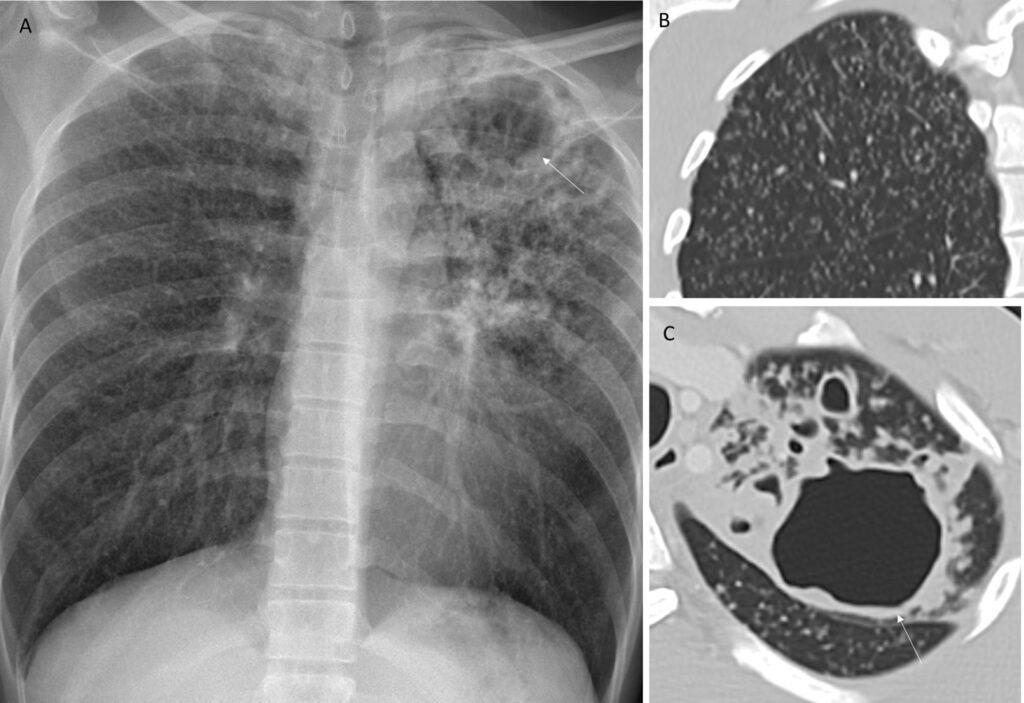

Resultatet er, at man på et røntgenbillede eller en CT-scanning ser et centralt, større område med betændelse (det oprindelige reaktiveringssted), omgivet af talrige små, satellit-noduler. Samlet set fremstår dette som en klynge af små noduler. På højopløselige CT-scanninger kan dette mønster ligne et træ med knopper og kaldes ofte for "tree-in-bud"-mønsteret, hvilket er et meget suggestivt tegn på en infektion, der spreder sig via de små luftveje.

- Røntgen af thorax: Ofte det første skridt. Kan vise en uklar fortætning eller en nodulær læsion, typisk i de øvre lungelapper, men detaljerne kan være svære at se.

- CT-scanninger: Er langt mere følsomme og detaljerede. En CT-scanning kan tydeligt visualisere den enkelte store nodul som værende sammensat af talrige mindre noduler og kan afsløre det karakteristiske "tree-in-bud"-mønster, hvilket styrker mistanken om tuberkulose.